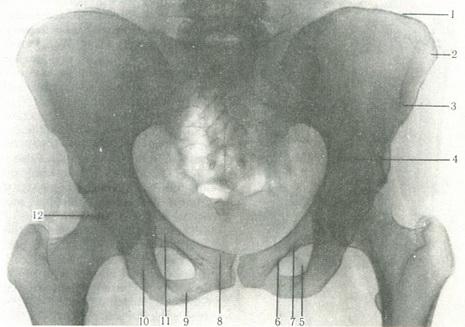

Знімки тазових кісток виробляють в задній, прямій і бічній проекціях. На знімку повинні бути видні кістки тазу, крижі, нижні поперекові хребці і тазостегнові суглоби (рис. 93). Посередині видно щілину симфізу (7-8 мм), праворуч і ліворуч - клубово-крестцовое зчленування. Чітко видно тазові кістки трикутної форми крижі, запирательное отвір, вхід у таз і щілину кульшового суглоба.

93. Рентгенограма тазових кісток дорослого.

1 - клубовий гребінь; 2 - передня верхня клубова ость; 3 - передня нижня ость; 4 - прикордонна лінія; 5 - верхня гілка лобкової кістки; 6 - нижня гілка лобкової кістки; 7 - запирательное отвір; 8 - лобковий горбок; 9 - гілка сідничної кістки; 10 - сідничний горб; 11 - гілка сідничної кістки; 12 - головка стегнової кістки.